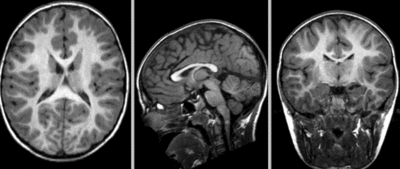

affine registered nonrigid registered (5,5,5 BSpline unmasked)

BSpline (7x7x7) unmasked

visualization of the nonrigid deformation component only